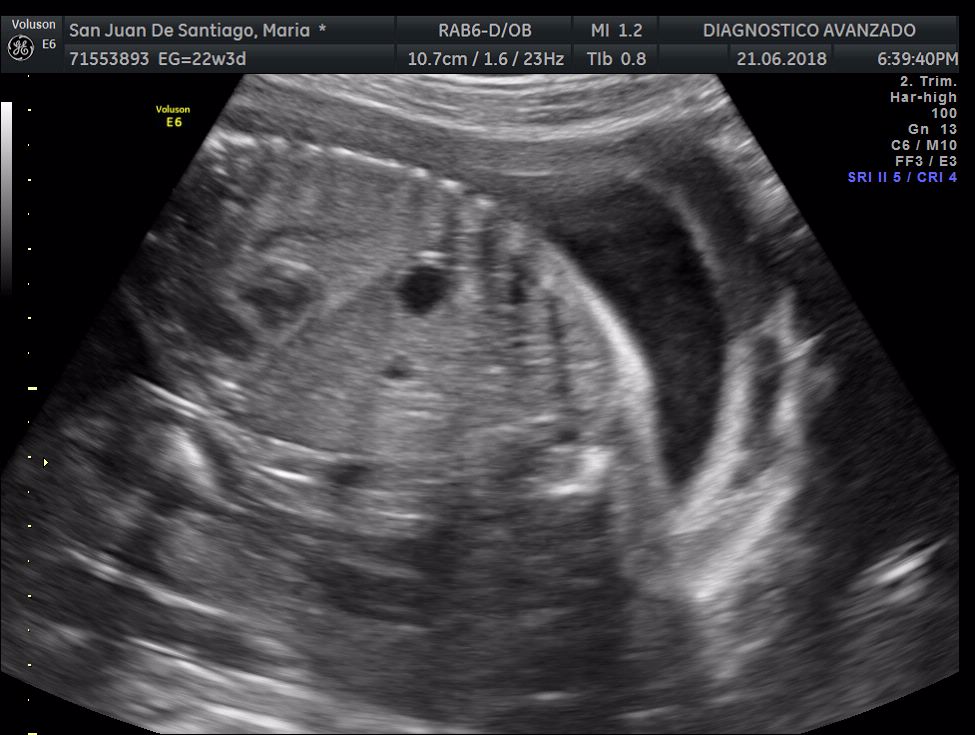

¡Hola a todos! Hoy hemos ido a hacer la tradicional ecografía 3D de la niña, os dejamos todo el material (aunque es un poco demasiado).